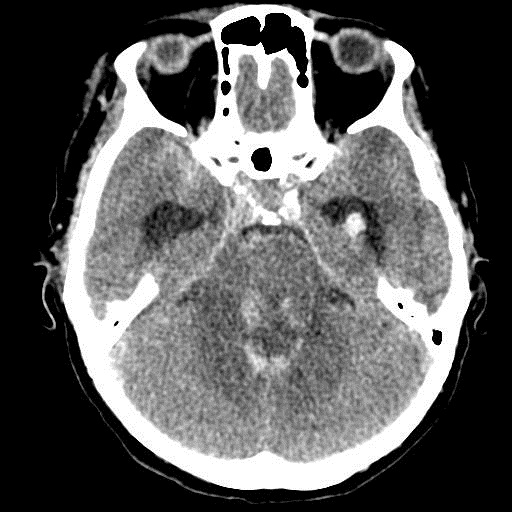

Острое внутримозговое кровоизлияние с выходом крови в желудочки (боковые - сгустки преимущественно в левом + эффект седиментации с горизонтальным уровнем жидкость\жидкость в задних рогах; сгустки крови в третьем желудочке, кровь в четвертом). Значительное увеличение височных рогов боковых желудочков - гидроцефалия. Смешение срединных структур вправо, отек белого вещества перивентрикулярно слева.

Довольно большие кровоизлияния в стволе мозга (что объясняет тяжесть состояния).

Дифференциация серого и белого в-ва сохраняется, хотя субарахноидальное пространство не прослеживается - проявление масс-эффекта, начальный этап отека мозга.

Остается вопрос по слегка гиперденсному (относительно серго вещества) однородному фокусу в левой лобной доле... и по причине кровоизлияния. Что касается последнего могу предположить патологию базилярной артерии (разрыв аневризмы?)... правда не вижу что-то крови в цистернах основания черепа.

Массивное медиальное кровоизлияние с прорывом в желудочки. Кровоизлияние в ствол. Признаки вклинения. В лбу может что-то и есть, но это не принципиально. А может быть и отечные извилины. Смущает, что нет масс-эффекта.

Про отек: субарахноидальных щелей совсем нет, по белому веществу и в стволе снижение плотности, извилины утолщены, серое вещество на этом фоне выглядит более светлым, толстым, подушкообразным.

Причина таких кровоизлияний, как правило, гипертензия и атеросклероз.